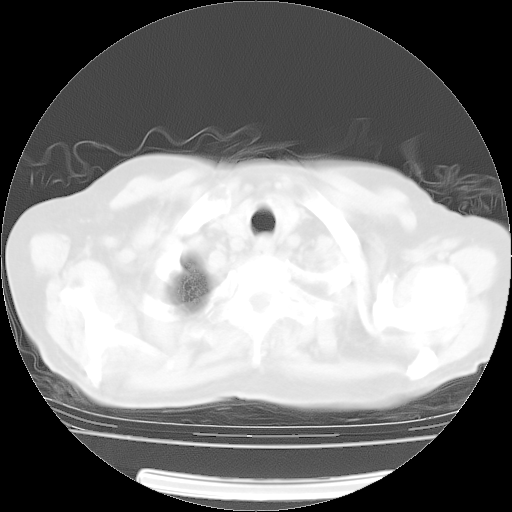

4月14日肺部CT

肺部CT平扫未见异常。